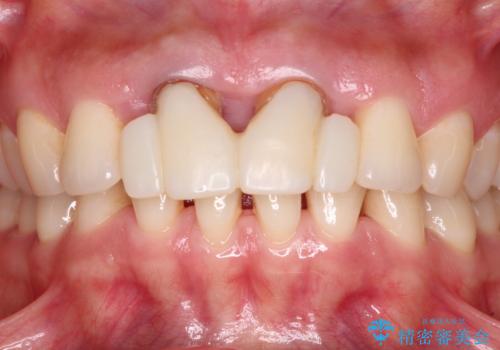

隙間をセラミックで閉じたら不格好で歯肉から出血 矯正治療と歯周外科で綺麗な前歯に

- 隙間の空いた前歯をセラミッククラウンで補隙したところ、歯肉から出血してしまい、何とかしたいとのことで来院された患者様です。

初めは前歯のみの処置で改善を希望されていたため、広範囲に処置範囲を広げることで歯の幅がバランスする治療を提案しましたが、削らなければならない歯が増えてしまうため、患者様と相談して全顎矯正により前歯のスペースを閉じていくこととしました。

不適合なクラウンが装着されていたため、歯周ポケットが深くなっていましたので、矯正治療前に歯周外科処置を行って歯周ポケットを除去し、矯正治療後にオールセラミッククラウンにて補綴治療を行うこととしました。

前歯の見た目はもちろん、出血や腫脹のない健全な前歯の状態を獲得することができました。